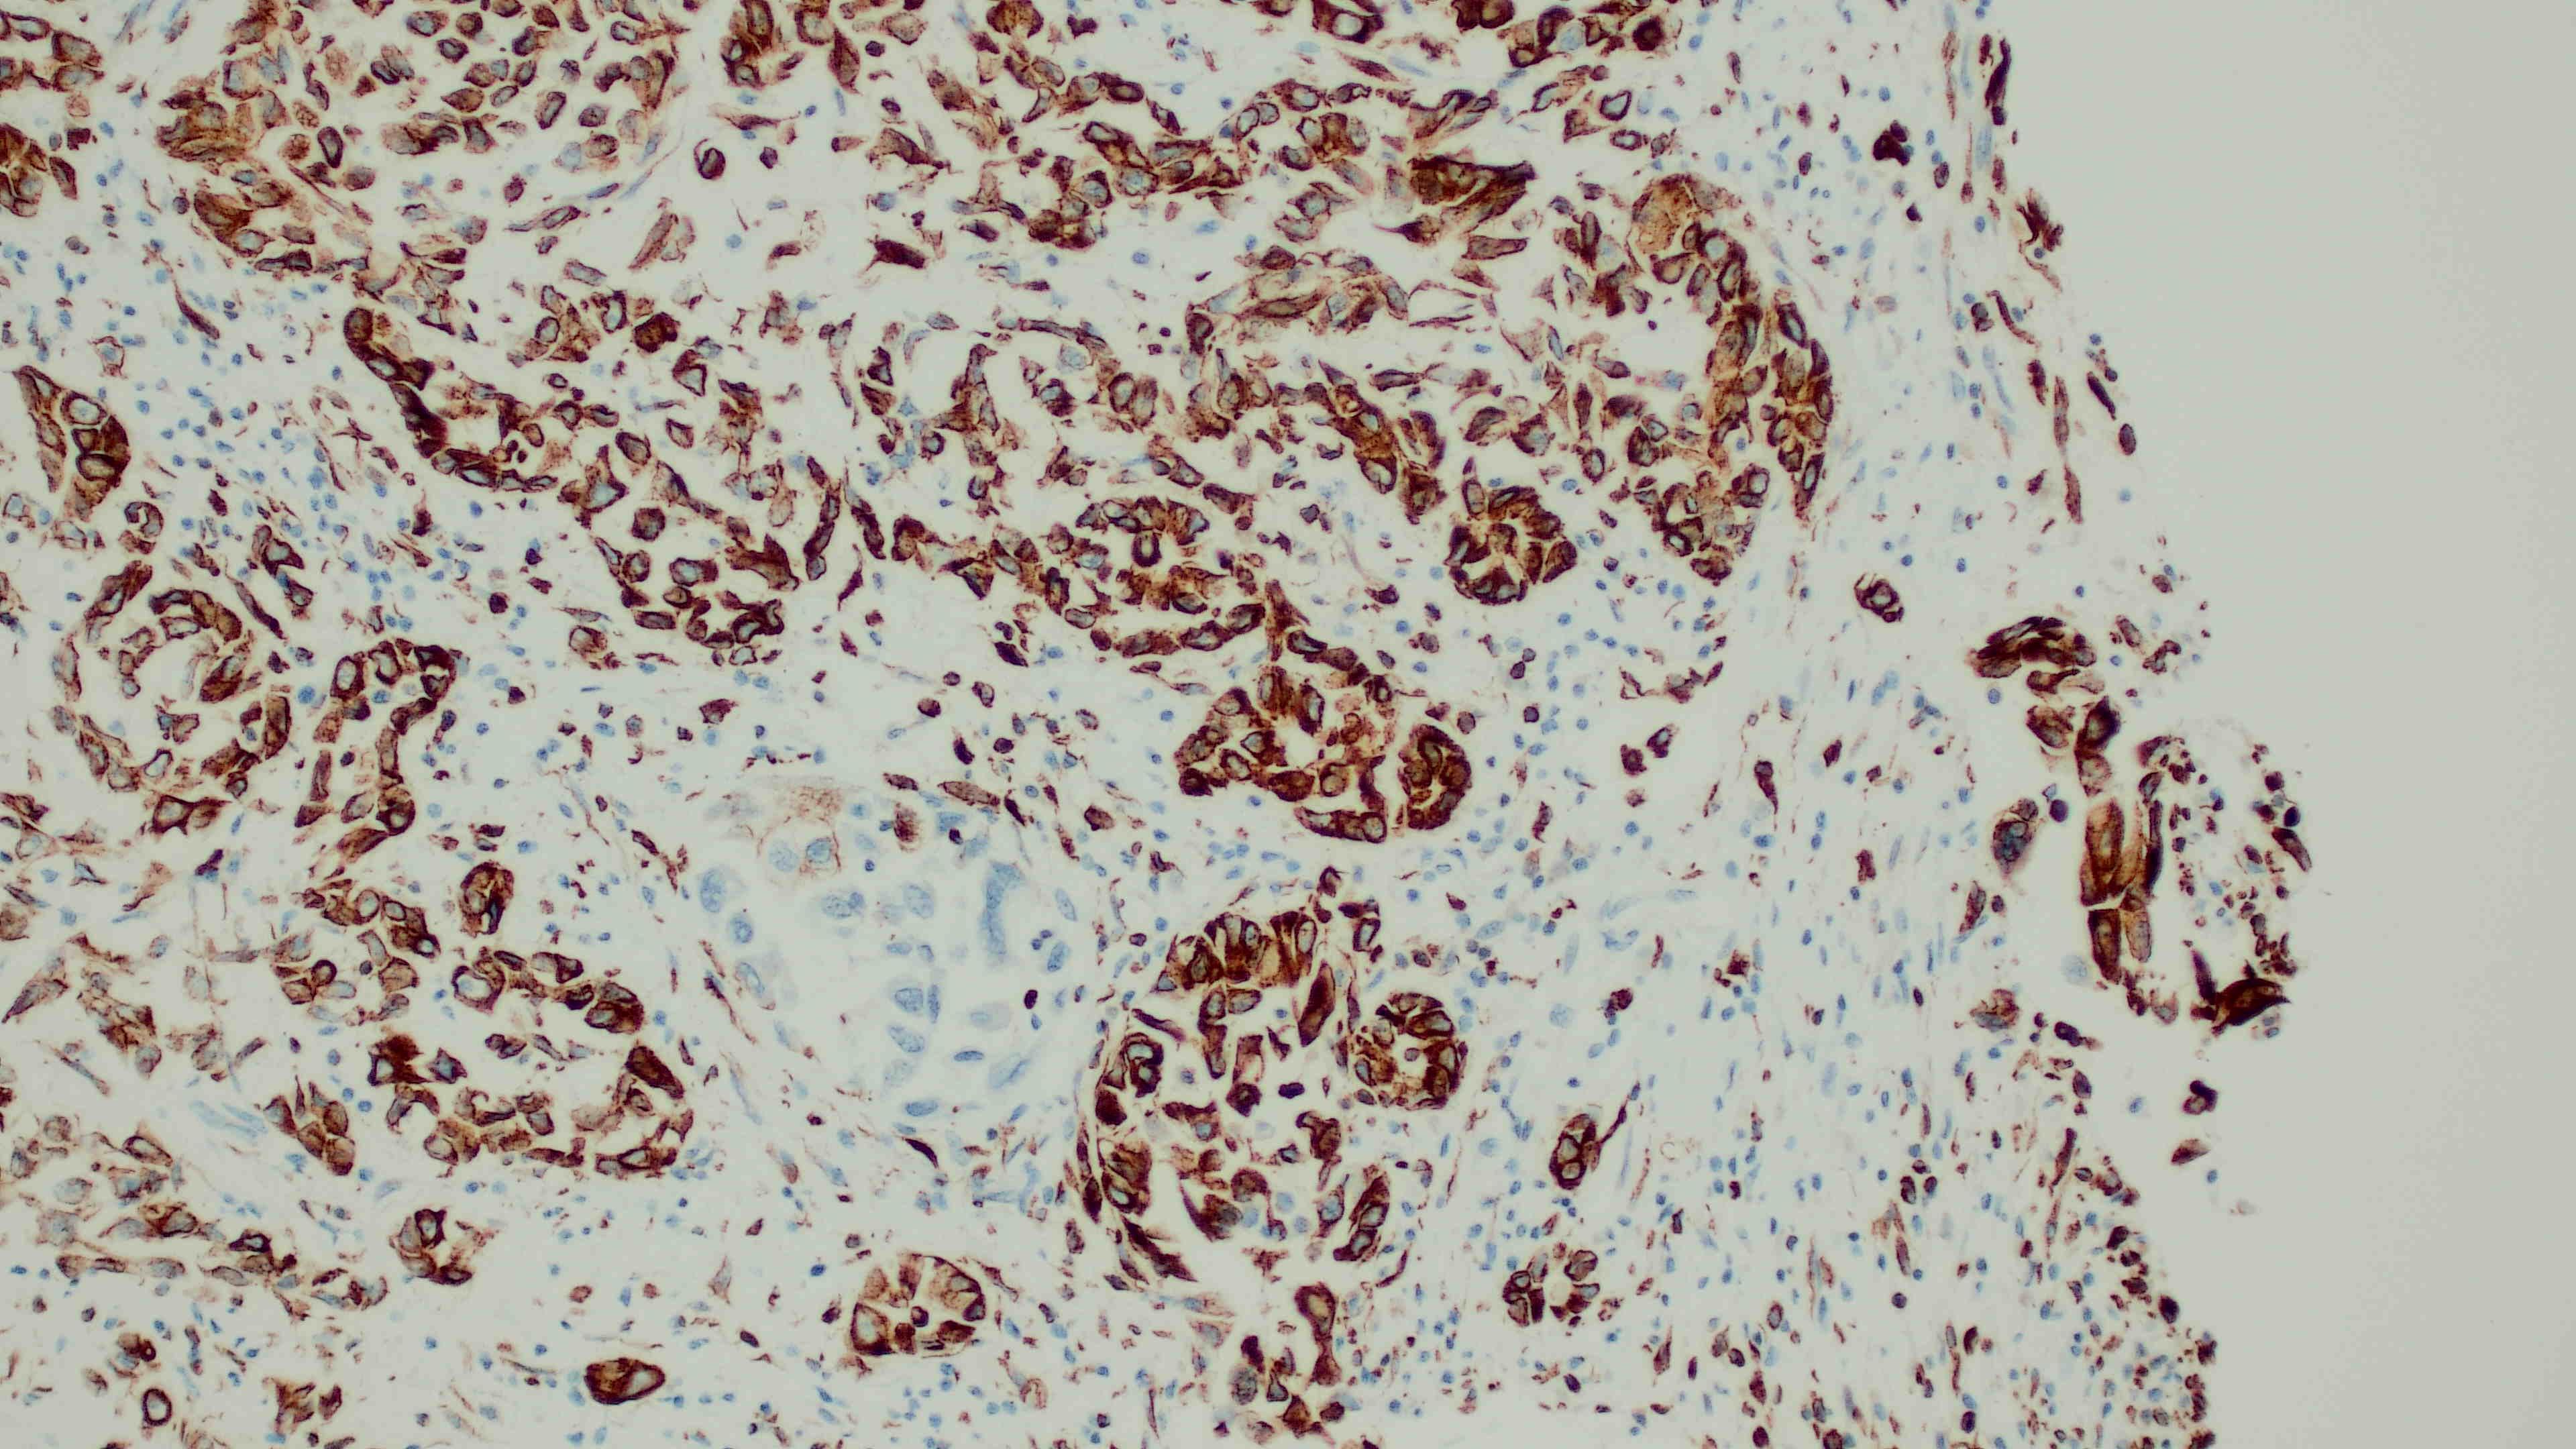

Immunohistochemistry: Neoplastic cells are diffusely strongly positive for vimentin. The majority of neoplastic cells are moderately positive for cytokeratin.

Postmortem examination revealed the presence of a neoplastic process within the pleural and peritoneal cavity, which on histopathology had a morphology most likely consistent with a mesothelioma.3,12 Additionally, the immunopositivity of both cytokeratin and vimentin, is consistent with a mesothelial origin, although rarely this dual positivity can be present in metastatic ovarian or renal carcinomas, which were not identified in this case.12

Mesothelial cells are somewhat unique amongst cell types for their dual immunoreactivity to both pancytokeratin and vimentin. During development, mesothelial cells differentiate from their mesodermal precursors, developing features of both epithelial and mesenchymal cells. With certain stimuli, mesothelial cells can undergo epithelial-to-mesenchymal transition (EMT) into other cell types, such as myofibroblasts, smooth muscle cells, and/or endothelial cells.3 This ability highlights their roles in repair and tissue formation following injury or inflammation.

While this immunohistochemistry (IHC) profile can be a useful feature for diagnosis, there are other neoplasms that can express dual positivity for pancytokeratin and vimentin when neoplastic cells undergo EMT. As mentioned by the contributor, this has been reported in metastases from both ovarian and renal carcinomas.16 It has also been documented in melanomas and aggressive metaplastic mammary carcinomas in humans.9 The absence of an additional primary neoplasm can help rule out other tumors, but there are other IHCs utilized in veterinary literature to assist in definitively diagnosing mesotheliomas. The JPC performed in-house calretinin and Wilms Tumor 1 (WT1) immunohistochemistry on this case post-conference, as both of these markers have been utilized in animal species to diagnose mesothelioma successfully.20 Unfortunately, neither of these IHCs worked on the donkey tissue in this case.